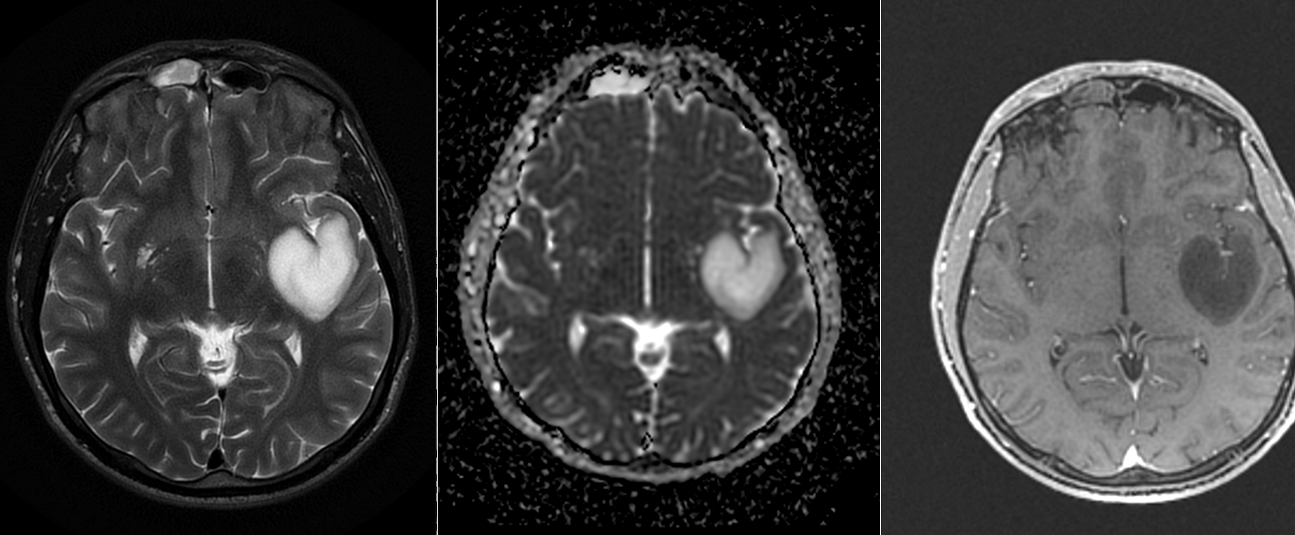

RMN cerebral cu contrast – metoda standard pentru caracterizarea glioamelor. Glioamele de grad mic apar ca leziuni hipointense pe T1, hiperintense pe T2, fără captare de contrast. În mod uzual se consideră că dacă un gliom de grad mic are o zonă cu priză de contrast pe RMN el este de grad III – anaplazic (grad înalt).